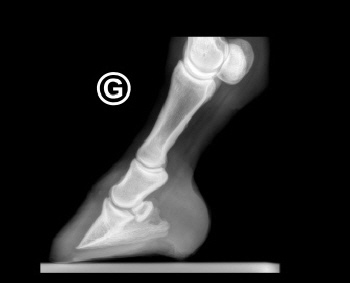

Röntgenbilder akuter- und chronischer Hufrehehufe vorher und nachher

Nachstehend stellen wir einige Röntgenbilder von Hufrehepferden ins Netz, welche das Vorher und das Nachher zeigen. Wir möchten damit aufzeigen, dass durch eine richtige Hufbearbeitung ein Hufbein wieder in eine korrekte Lage innerhalb der Hornkapsel zu liegen kommen kann.

In besonders schweren Fällen wurde doch zumindest eine Optimierung angestrebt.

vorher